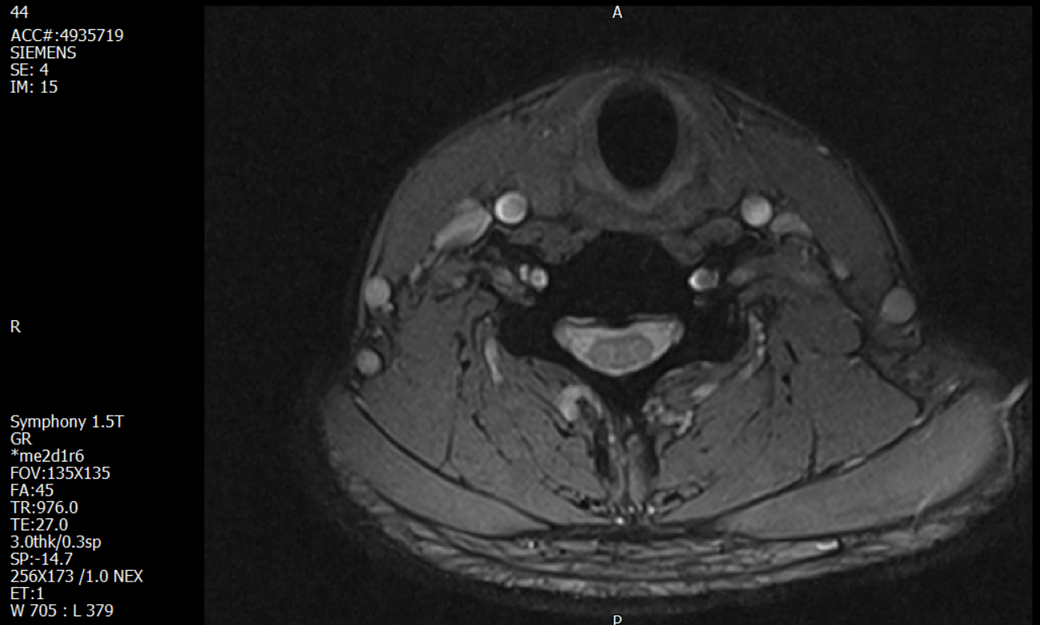

경추 요추 디스크 MRI판독 부탁드립니다.

- 3개월전 좌측 상지 저림(힘빠짐) 발생. 이틀뒤 에 좌측 하지 저림(힘빠짐) 발생.

-11월, 증상발생 직후 잠실소재 척추전문병원 MRI 요추경추 촬영 후 신경외과 박사 진료, 허리는 매우 건강, 경추는 퇴행성 진행되고 있지만 디스크라고 보기 어려움. 신경막만 살짝 건드리는 정도고 이 정도로 힘빠짐이나 저림이 오지 않고 원인은 다른 곳에 있을 가능성.

1. MRI 상 , 경추와 요추에 디스크가 있나요? 있다면 좌측 팔과 다리에 저림 및 힘빠짐을 줄 정도인가요?

• 4번 째 사진

• 1. MRI 사진을 보았을 때 디스크를 의심해볼 수 있는 소견이 살짝살짝 보이긴 합니다만, 상하지의 저림 및 힘빠짐을 유발할 정도인지는 솔직히 회의적입니다.

2. 영상의 퀄리티는 나쁘지 않아 보입니다. 굳이 재촬영을 하실 필요는 없어 보입니다.

3. 개인적으로는 디스크로 인한 증상이 아닐 것으로 보나, 만약 디스크가 맞다면 우연하게 목과 허리 디스크 발병이 이틀 간격을 두고 나타났을 가능성을 생각해야 하는데, 현실적으로 그 가능성이 높지 않습니다.

4. 말씀하신 것처럼 특히 요추부 MRI는 디스크를 찾기 어렵습니다.

상기 MRI 소견으로는 심한 증상을 보일 정도는 아니며 디스크의 가능성은 적어보입니다.